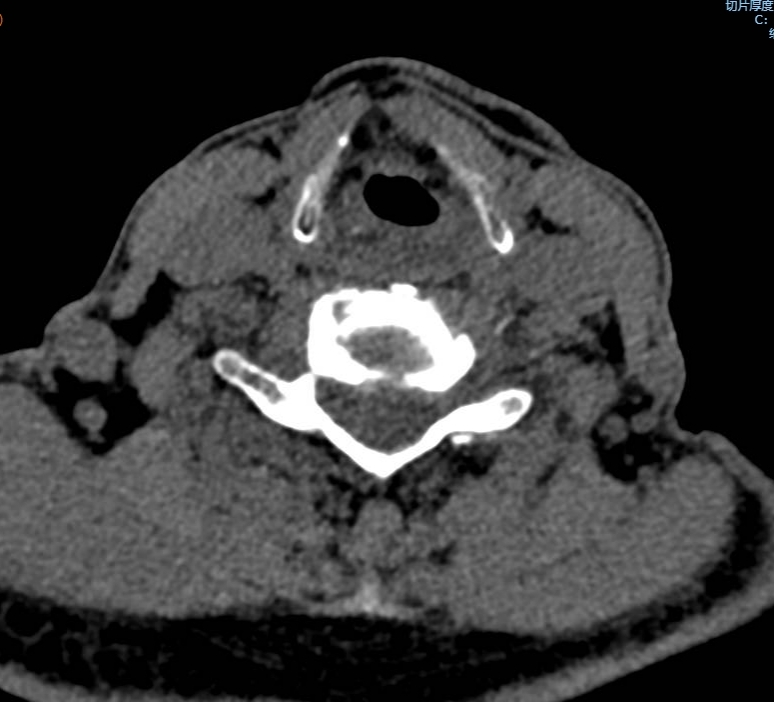

手术之后3天,黄大伯疼痛得到很好缓解,露出了许久没有的笑容,终于可以安心躺着睡觉了,1个月后基本恢复了正常生活,6个月后复查CT发现突出的颈椎间盘已经基本消失了,黄大伯一家人对治疗效果非常满意。

手术之前CT,巨大突出物 术后6个月复查CT:突出物消失